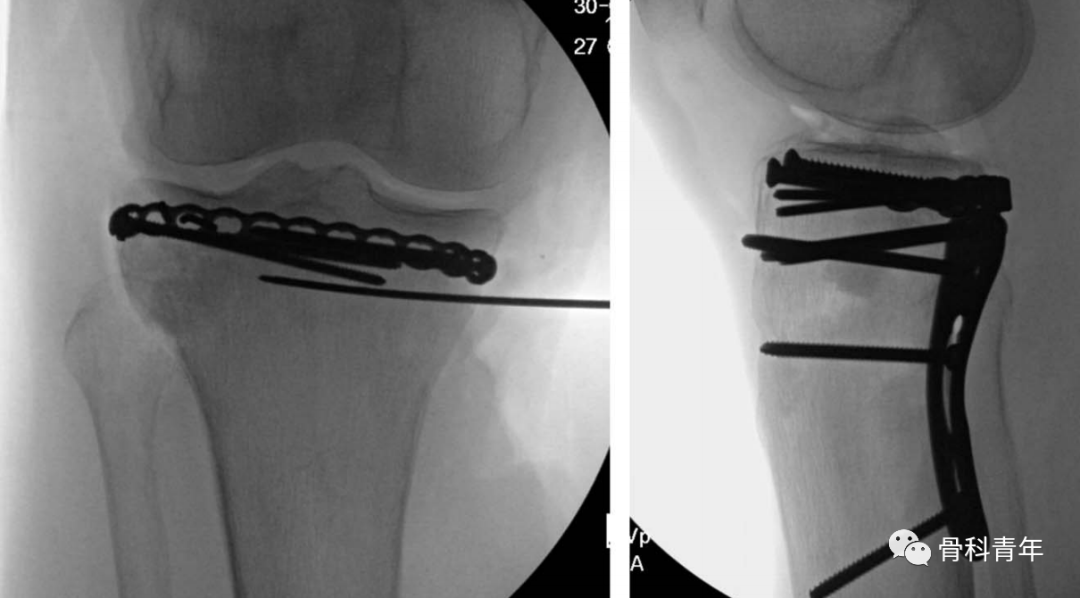

在复位满意后,将环形钢板塑形,通过平台后方建立的软组织隧道,穿出至外侧,并在外侧采用2枚2.7mm螺钉临时固定。

步骤4:点式复位钳拉紧环形钢板后,在内侧置入2枚2.7mm普通螺钉固定。关节面直视下及C臂机辅助下,评估复位情况及钢板位置情况。